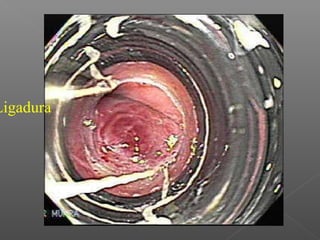

Ligadura endoscópica de varices esofágicas.

Ligadura

Manejo: Prevención de sangrado: ›betabloqueo › ligadura Tratamiento de sangrado: › Escleroterapia › ligadura › farmacológico Prevención de resangrado: › Endoscópico › farmacológico

Ligadura endoscópica devarices esofágicas.